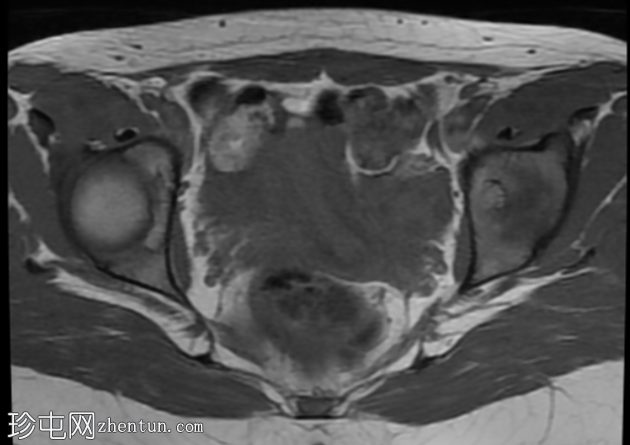

轴位

DWI序列

子宫前倾位,分区解剖结构正常。矢状位序列可见子宫前壁肌层局灶性边界不清的低信号病灶,但在后续序列中未见明显,符合短暂的生理性子宫肌层收缩表现。

双侧卵巢大小及卵泡活动均正常。未见囊性或实性肿块。

该病例的盆腔器官MRI表现与患者年龄(14岁)相符,子宫位置正常,分区解剖结构正常,双侧卵巢大小及卵泡活动均正常,未见囊性或实性肿块。

此外,MRI还意外发现子宫肌层局灶性病变,T2信号低,易被误诊为子宫肌瘤。然而,该病变在后续序列中消失,符合短暂的生理性子宫肌层收缩所致。